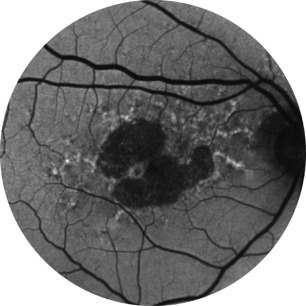

Baseline Year 1

BCVA 20/63+, GA Area 5.18 mm2

Baseline Year 2

BCVA 20/80-2, GA Area 10.39 mm2

Baseline Year 5

BCVA 20/200, GA Area 18.58 mm2

Images courtesy of David Elchenbaum, MD, Retina Vitreous Associates of Florida.

BCVA = Best-corrected visual acuity.